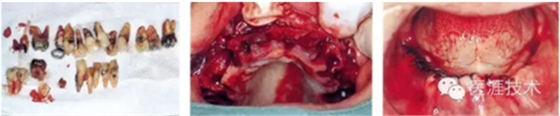

09,全口拔牙,并做牙槽修整,縫合

完成后的治療用臨時(shí)義齒

10,治療用臨時(shí)義齒修整后粘膜面使用組織面調(diào)解劑進(jìn)行加墊